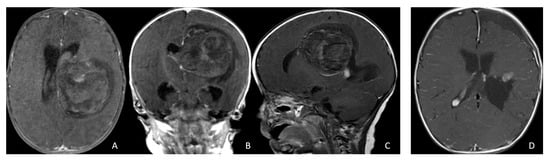

Open AccessReview

The integration of molecular features into histopathological diagnoses has become central to the World Health Organization (WHO) classification of central nervous system (CNS) tumors, improving prognostic accuracy and supporting precision medicine. However, unequal access to molecular testing limits the universal application of integrated diagnosis. To address this, artificial intelligence (AI) models are being developed to predict molecular alterations directly from histological data. In gliomas, deep learning applied to whole-slide images (WSIs) of permanent sections achieves neuropathologist-level accuracy in predicting biomarkers such as IDH mutation and 1p/19q co-deletion, as well as in molecular subtype classification and outcome prediction. Recent advances extend these approaches to intraoperative cryosections, enabling real-time glioma grading, molecular prediction, and label-free tissue analysis using modalities such as stimulated Raman histology and domain-adaptive image translation. Beyond gliomas, AI-powered histology is being explored in other brain tumors, including morphology-based molecular classification of spinal cord ependymomas and intraoperative discrimination of gliomas from primary CNS lymphomas. This review summarizes current progress in AI-assisted molecular profiling prediction of brain tumors from tissue, highlighting opportunities for rapid, accurate, and globally accessible diagnostics. The integration of histology and computational methods holds promise for the development of smart AI-assisted neuro-oncology.